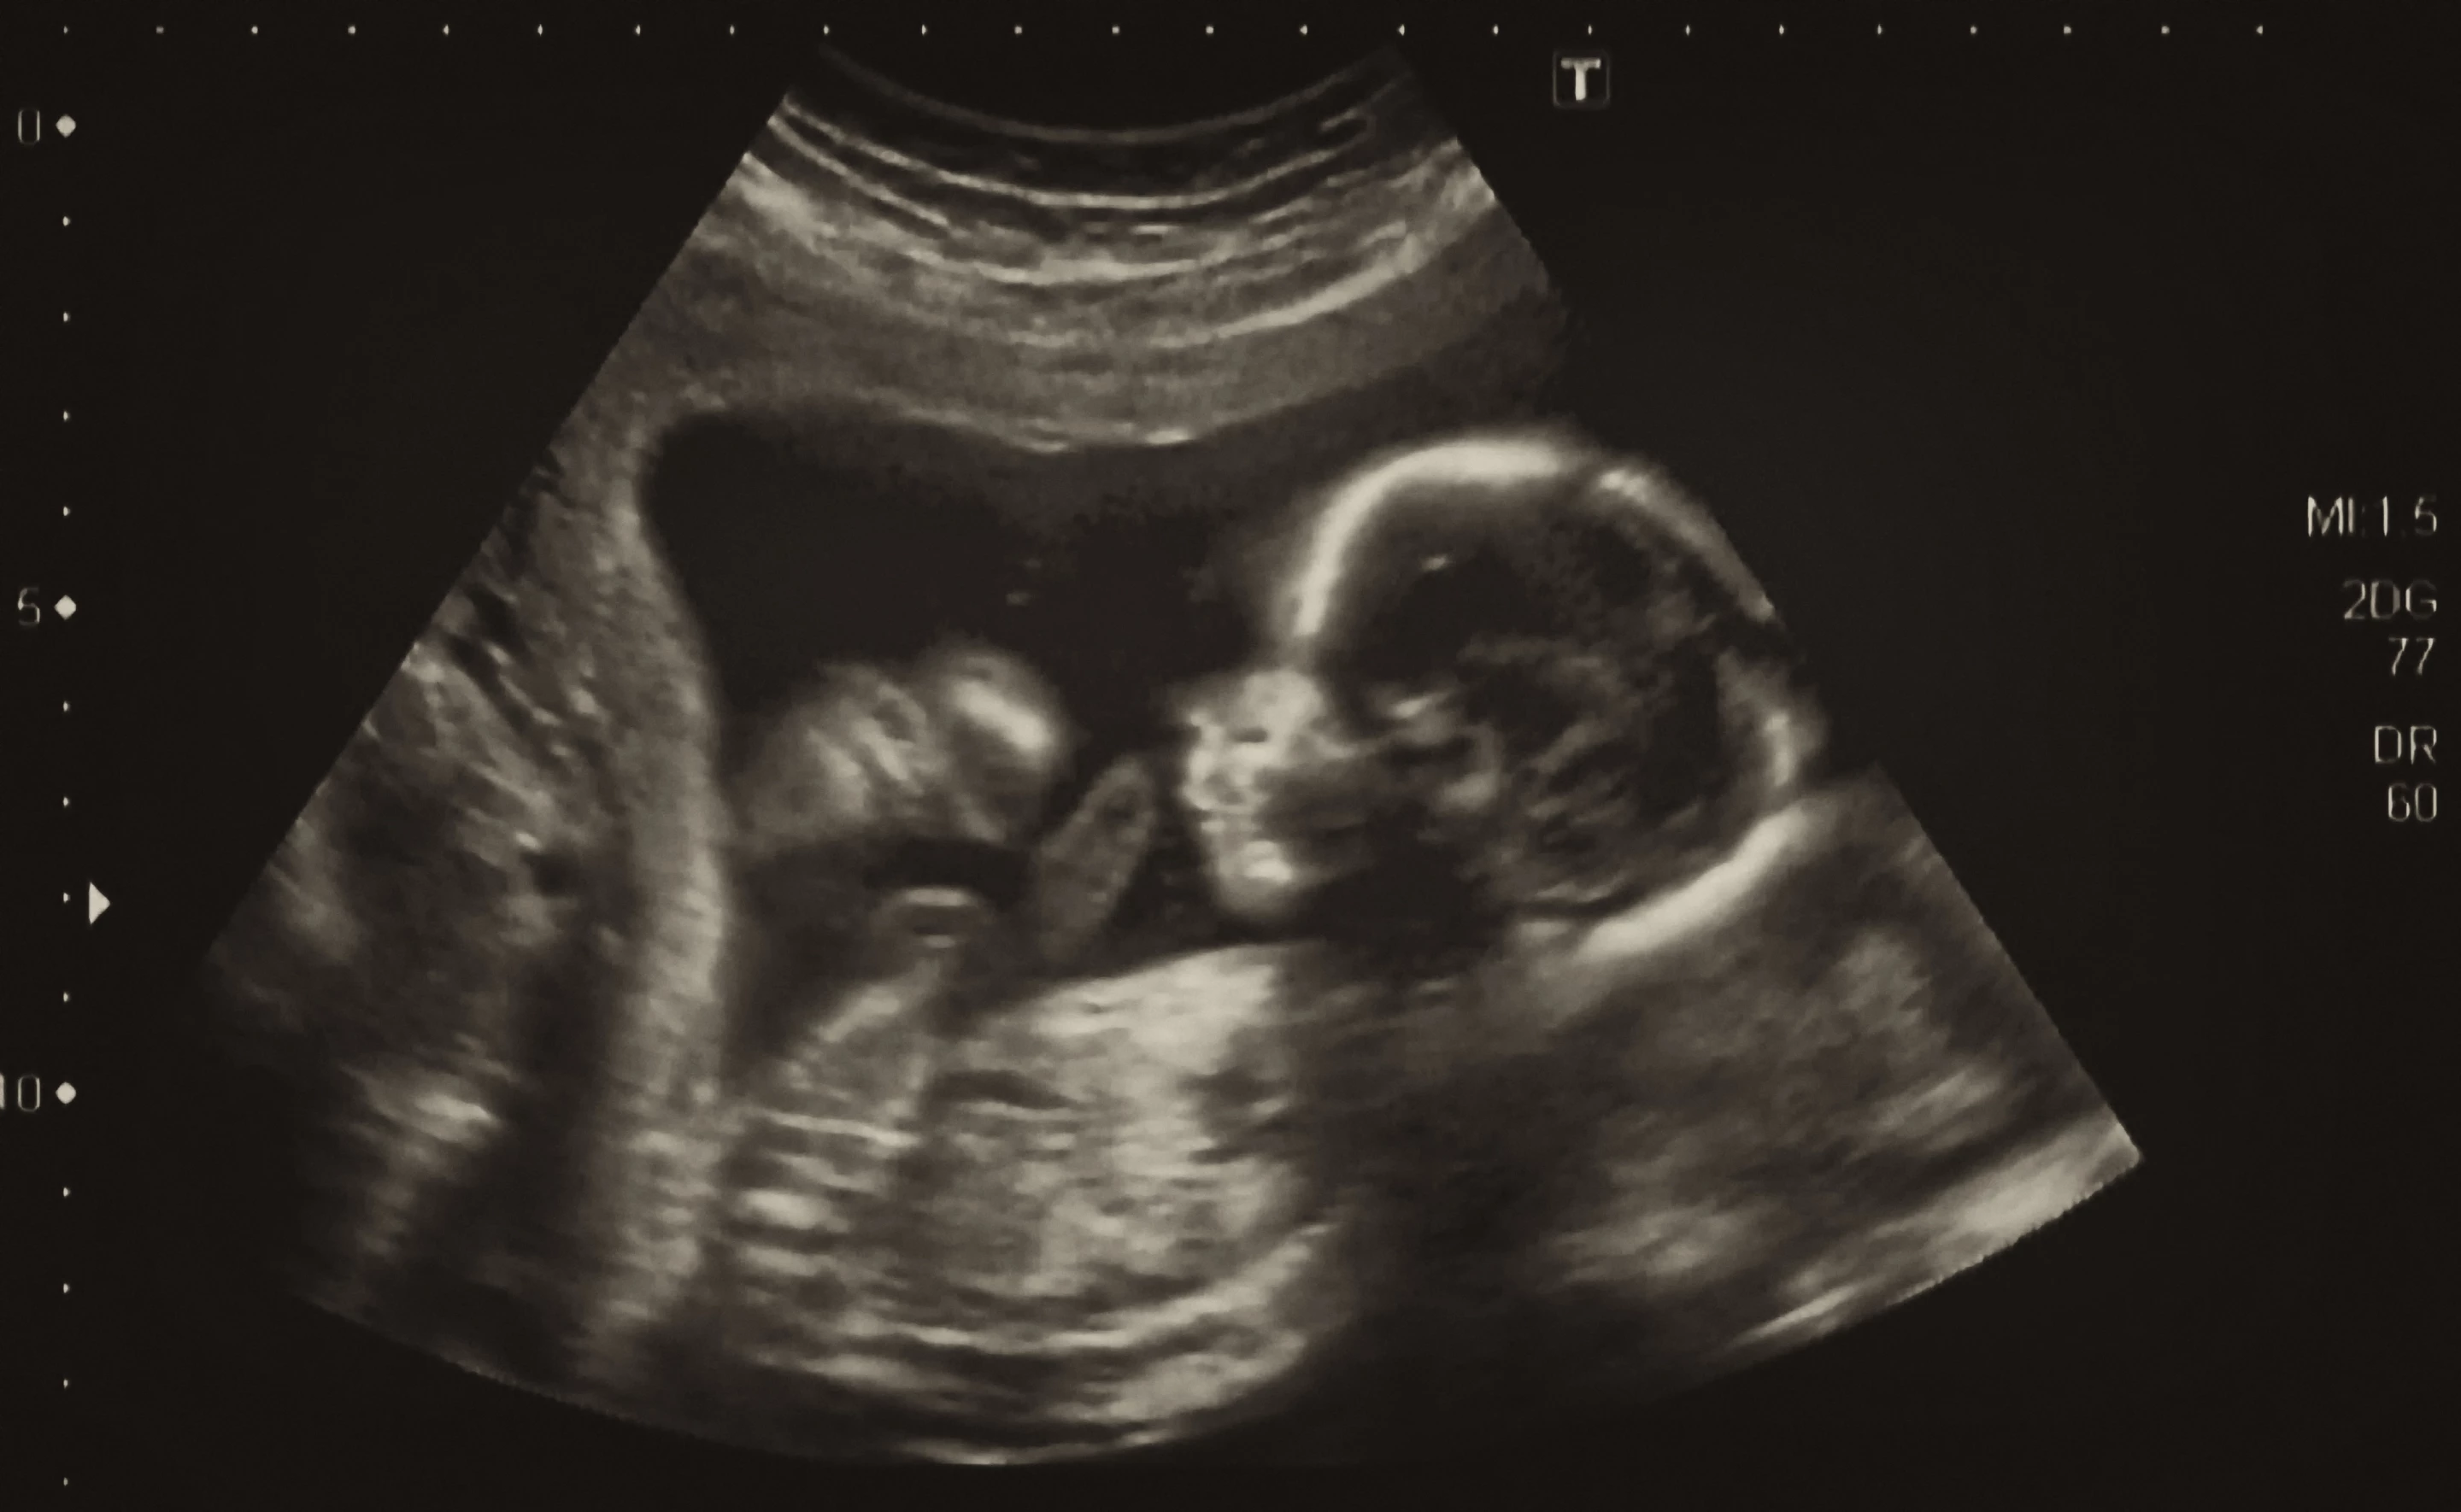

Surgeons have successfully performed a first-of-its-kind procedure in utero to treat a potentially fatal genetic defect in the brain. Usually treated after birth, the new procedure could give newborns a better chance of a normal life.

So for the first time, surgeons at Brigham and Women’s Hospital and Boston Children’s Hospital have now performed a VOGM embolization in utero, guided by ultrasound. While in the womb, placental circulation takes the stress off the fetus’ heart and brain, protecting them from damage. The hypothesis was that performing the procedure before birth could improve outcomes.

The team performed the procedure on a fetus at 34 weeks and two days gestation, and appears to have been successful. The baby was born in mid-March and MRI scans showed no signs of stroke, fluid buildup or hemorrhage, which are common symptoms of VOGM.